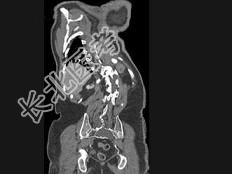

- 单项选择题男,24岁, 四肢细长,蜘蛛指, 肌张力降低,结合图像, 最可能的诊断是 ( )

C、马方综合征